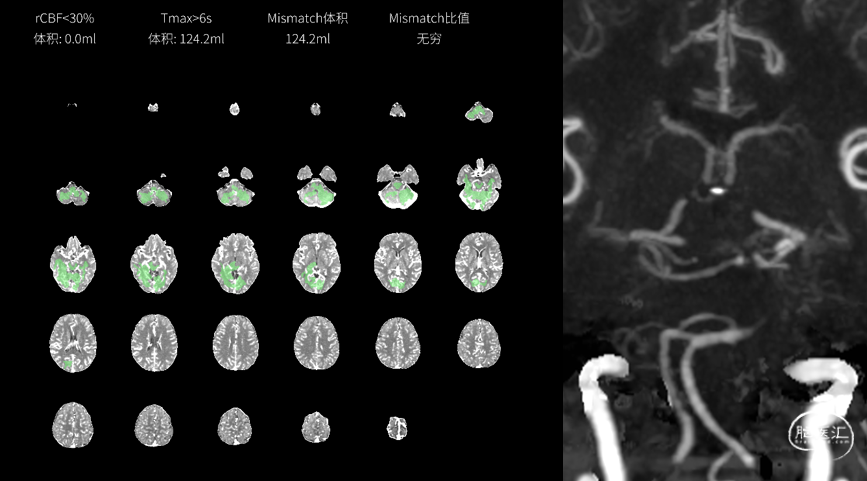

现病史:患者无明显诱因出现右侧肢体乏力、麻木,行走不稳,言语含糊,吐字不清,讲话费力,伴头昏不适,无恶心、呕吐,无意识障碍、大小便失禁,送至急诊。接诊病人时见患者言语含糊、右侧肢体无力,患者立即完善抽血查血常规、肝肾功、电解质、凝血全套未见明显异常,随后完善颅脑CT平扫未见高密度影,考虑为急性脑梗死,患者发病在静脉溶栓时间窗内,有静脉溶栓指征,与患者家属沟通同意并签署静脉溶栓同意术后,予阿替普酶63mg静脉溶栓治疗,溶栓中无特殊不适,完善头部CTA提示头颅CTA:基底动脉上段闭塞,右侧大脑后动脉多处狭窄、显影浅淡;右侧椎动脉V5段动脉粥样硬化、纤细;考虑双侧颈内动脉C4-7段粥样硬化。头颅CTP:右侧颞枕叶MTT、TTP稍延长。有急诊行“全脑血管造影术+必要时血管内治疗”的指征,向家属交代手术的必要性,同时告知血管介入治疗可能存在的高风险及严重不良预后,家属经慎重考虑并签署手术同意书后,由急诊直接送入急诊导管室行“全脑血管造影术+必要时血管内治疗”,术后以“急性脑梗死”收入我科,病来患者精神欠佳,未进食、未睡眠,大小便正常,体重近段时间无明显增减。

患者经脑血管造影检查见:基底动脉中远段次全闭塞,结合患者多模CT检查结果,有急诊血管再通手术指征。但术中可能出现血管成形失败;术中血栓形成、斑块脱落、气栓等导致新发脑梗死;术中可能出现基底动脉穿支闭塞导致脑干梗死;术中可能出现导丝、导管损伤血管导致血管夹层、脑出血;术后可能出现血管再闭塞;术后可能出现再灌注损害导致脑水肿、脑出血;另外术中、术后可能出现其他难以预料的手术风险。上述情况均有可能导致患者神经功能损害进一步加重,甚至危及生命,必要时需要补救性手术治疗。将上述情况告知患者家属后,家属经慎重考虑后同意行血管成形手术治疗。给与替罗非班负荷剂量后持续微量泵泵入。